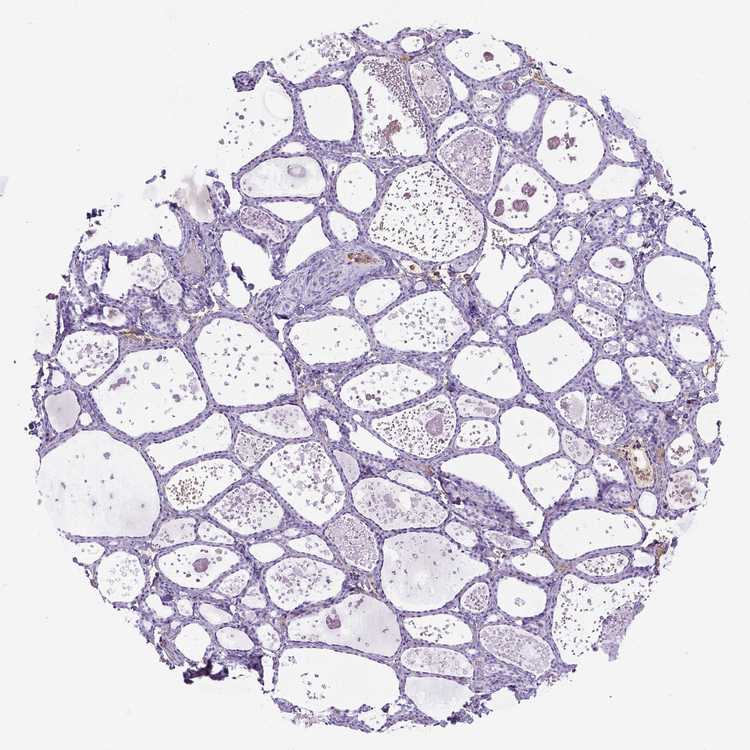

THYROID GLAND - Antibody stainingi

Antibody staining in the annotated cell types in the current human tissue is reported as not detected, low, medium, or high, based on conventional immunohistochemistry profiling in selected tissues. This score is based on the combination of the staining intensity and fraction of stained cells.

Each image is clickable and will lead to virtual microscopy that enables deeper exploration of all samples and also displays staining intensity scores, fraction scores and subcellular localization as well as patient and tissue information for each sample.

Antibody HPA001835Antibody HPA003948Antibody CAB072872

Glandular cells Not detectedNot detectedNot detected